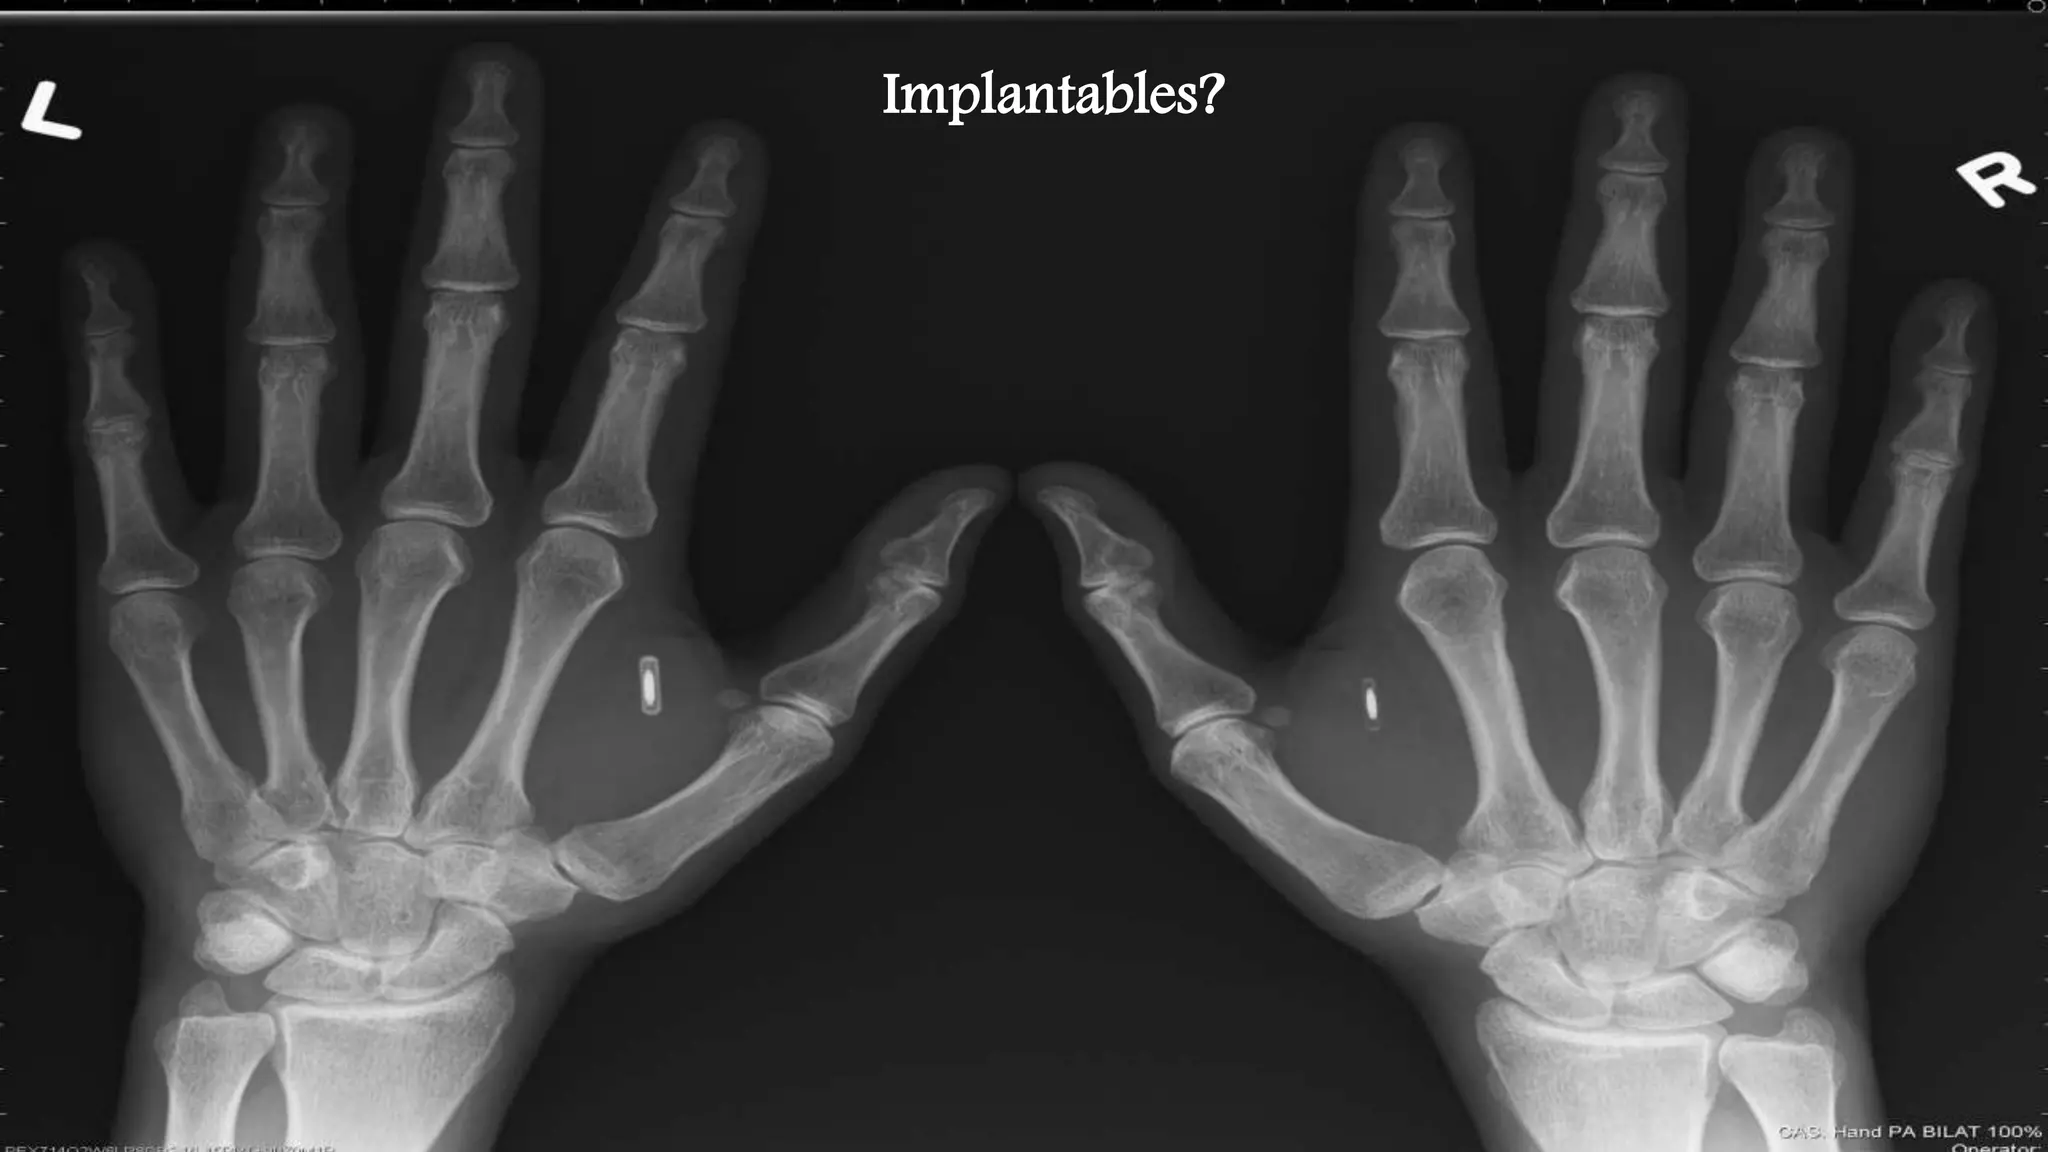

Implantables?

• #41 Implantables?